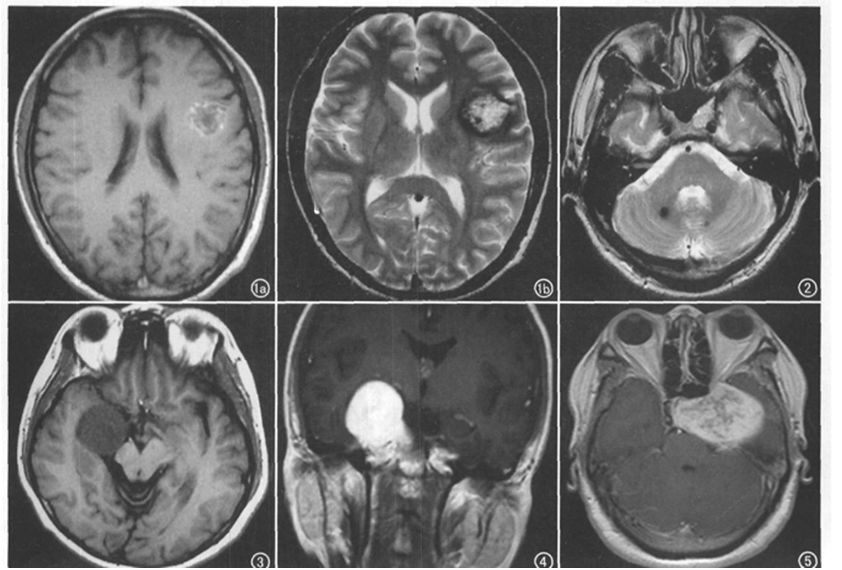

典型海绵状血管瘤两例,分别是额叶和海绵窦的